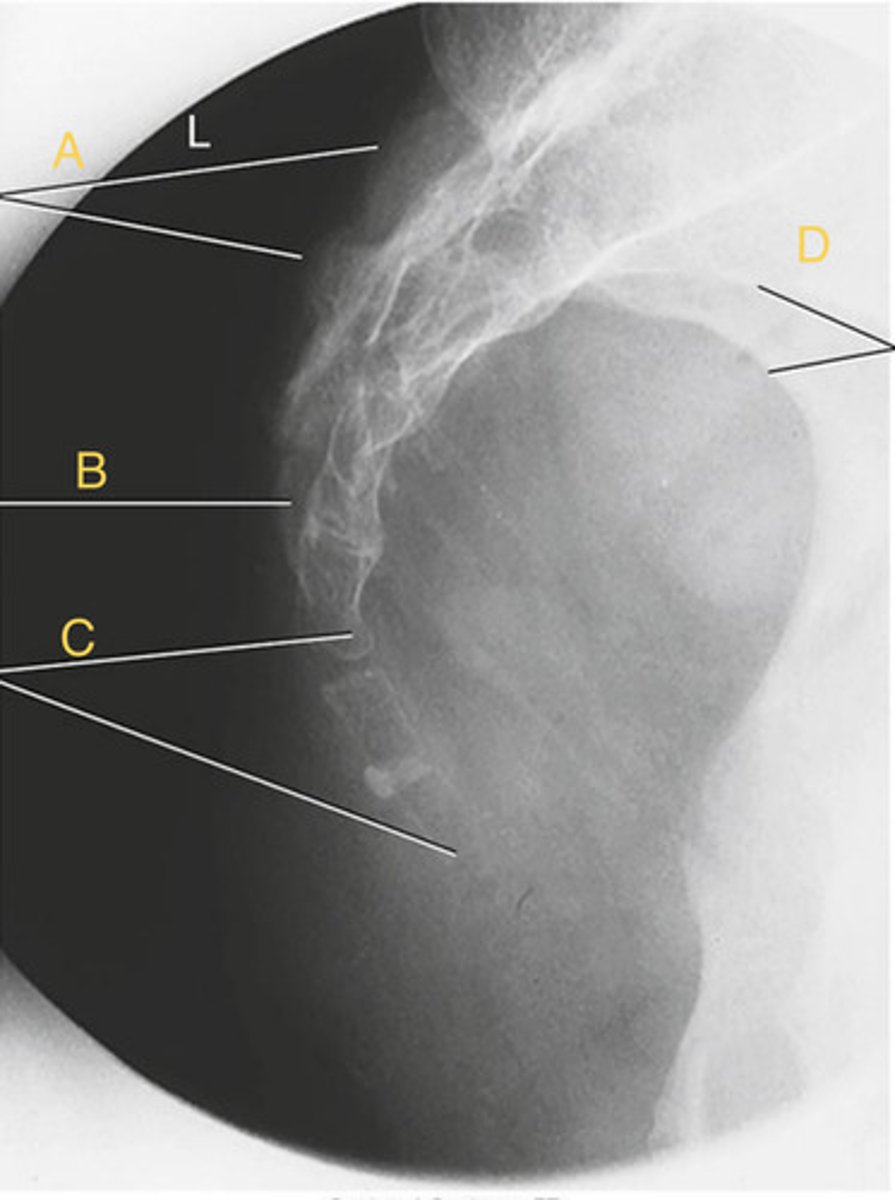

T3-4 intervertebral disk space

B.

T4 transverse process

C.

T5 Pedicle

D.

T7 spinous process

E.

T11 costovertebral joint

F.

T11 inferior articular process

G.

T12 superior articular process

H.

L 1st rib

I.

L 3rd posterior rib

J.

L 9th posterior rib

K

T3 body

A.

T12 floating rib

L